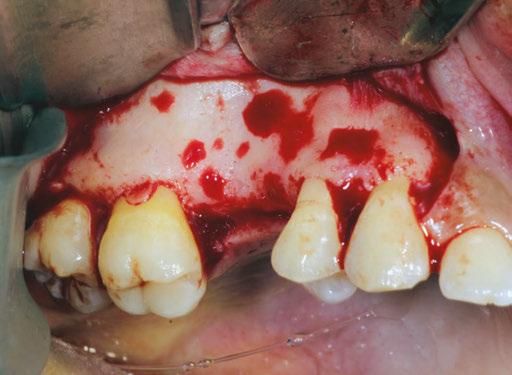

Figure 1: Full-thickness flap raised to gain access to the lateral wall of the sinus (Two-stage sinus augmentation procedure using Garg sticky bone™) Figure 2: The sinus membrane is detached to proper height from the medial wall of the sinus (Two-stage sinus augmentation procedure using Garg sticky bone™)

Figure 4: The sinus cavity is completely grafted with Garg sticky bone until the material is flush with the level of the original lateral wall (Two-stage sinus augmentation procedure using Garg sticky bone™)

Garg sticky bone™ can be used effectively in place of liq uid PRP in sinus grafting, as shown in Figures 1 to 5. In this procedure, the lateral sinus wall is exposed via a broad-based, full-thickness mucoperiosteal flap, extending from the maxil lary tuberosity to a releasing incision in the canine fossa region. The flap should extend superiorly to just below the infraorbital foramen to provide access to the lateral wall of the sinus. A large oval finishing bur or diamond bur is used to create an oval hole in the lateral cortical bone for access to the sinus membrane. To preserve its integrity, the sinus membrane is directly reflected in a series of stages, beginning at the sinus floor — superiorly, anteriorly, and posteriorly around the edges of the oval entry — until the sinus membrane is completely elevated posteriorly to the tuberosity. PRP sticky bone is intro duced into the sinus to augment the alveolar ridge height. Note its excellent handling qualities. A PRP membrane can be used to close the oval window of the lateral sinus wall once the graft is in place.6